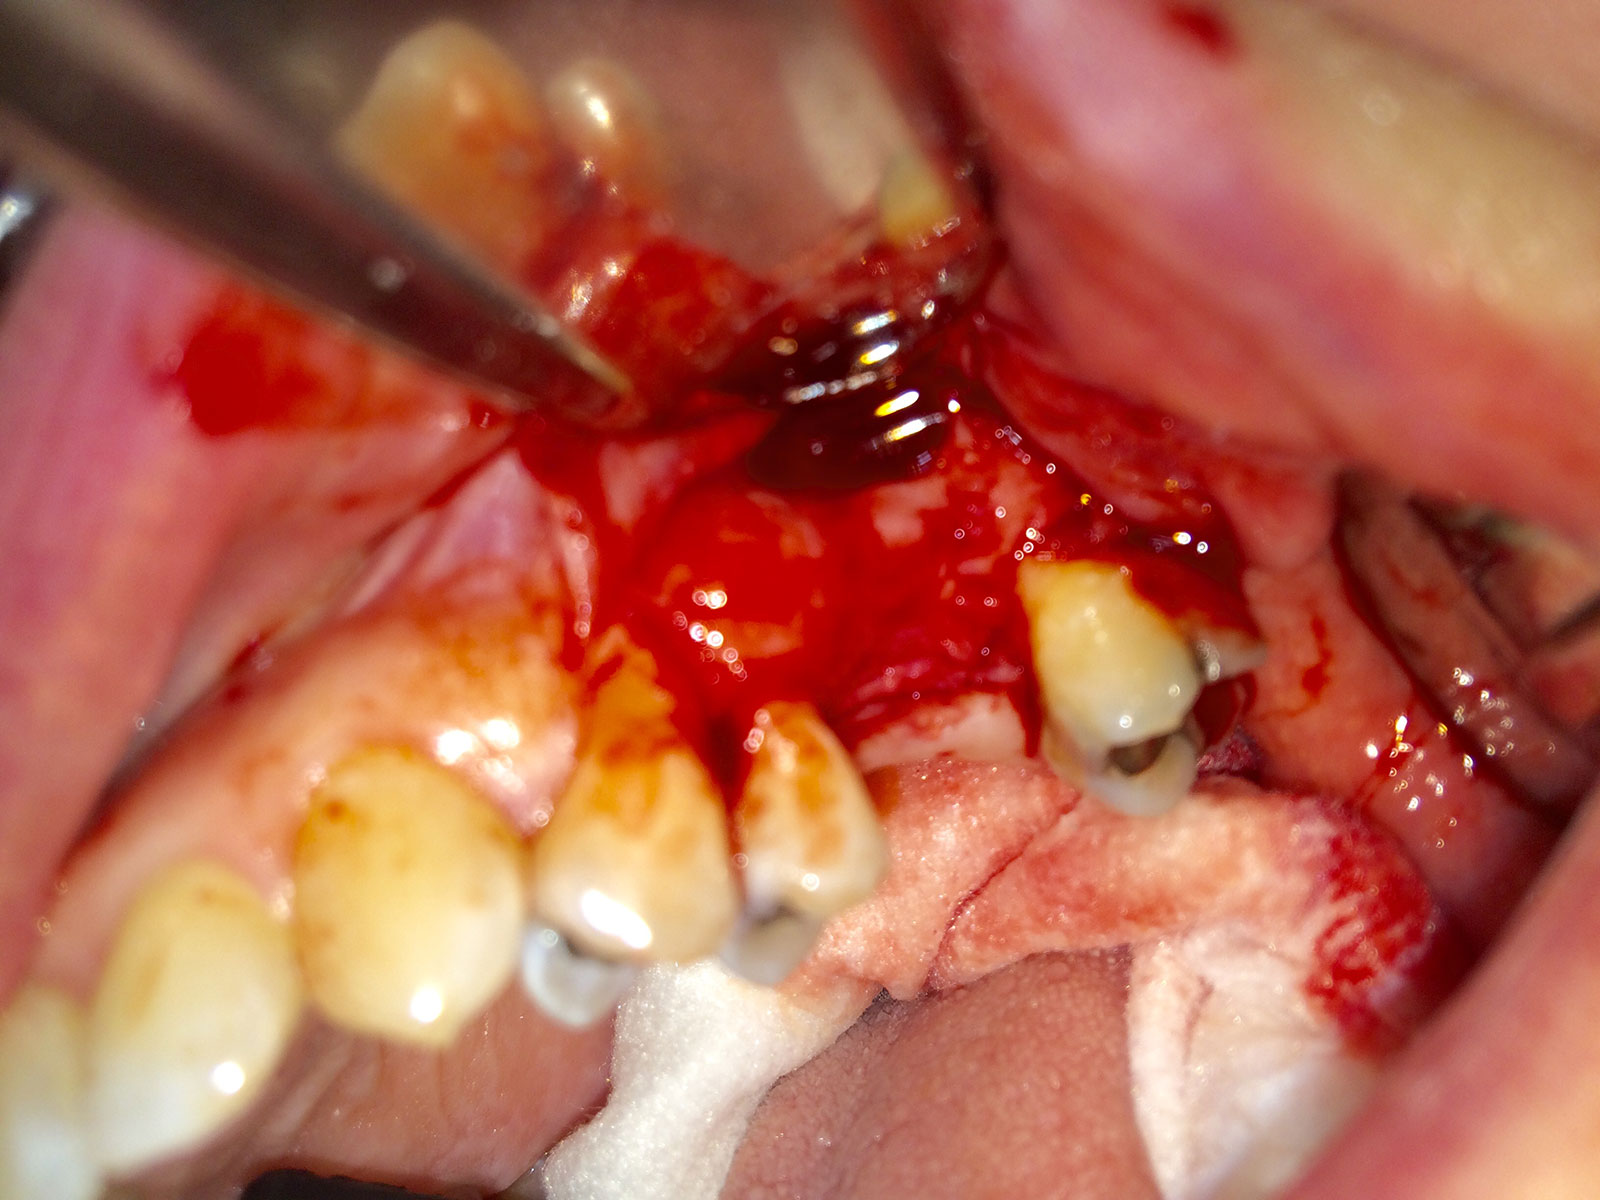

Sinus Grafting Procedures

A sinus grafting procedure, also known as a sinus augmentation, is for patients who have insufficient natural bone in the areas where dental implants are needed. They are long lasting, strong and sturdy, and fit and function like natural teeth. The procedure involves adding bone, either your own natural bone from another part of the body, from a donor or made of processed or synthetic bone material, and placing it below the sinus so that the implants can be placed. After the bone has healed and developed, usually around four to 12 months, the dental implants can be placed.

The photos on this website are from real surgeries performed by Dr. Ulloa. Due to the

graphic nature of the images and content, viewer discretion is advised.

Click to enlarge images